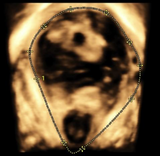

d) poruchami hojení jizev na děloze po císařském řezu (tzv. niche)